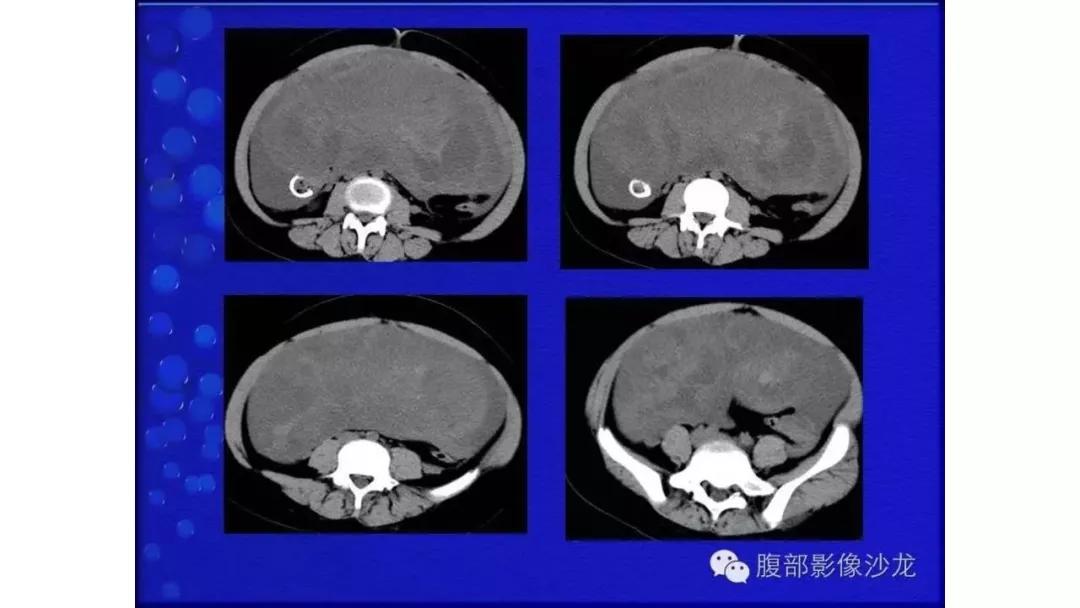

病理:浆液性囊腺癌

病理:颗粒细胞瘤